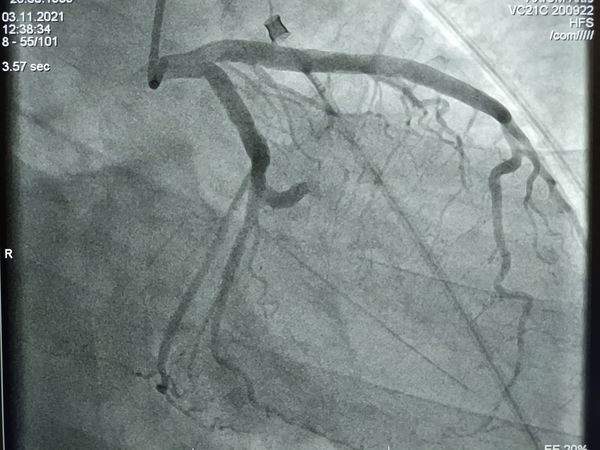

Через 10 минут после поступления в больницу пациенту сделали коронарографию: под местным обезболиванием прокололи артерию, через неё и сосуды сердца провели специальные трубки и с помощью контраста и рентгеновского излучения проверили проходимость артерий сердца. Исследование показало тромбоз (закрытие) огибающей артерии, т. е. кровь по ней не поступала к сердцу.